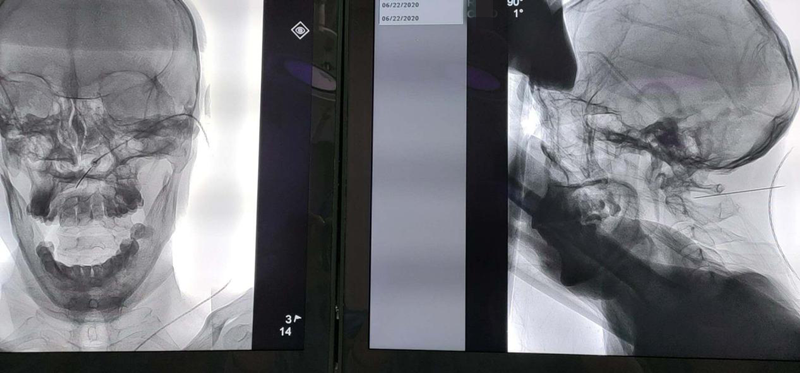

原来,1个月前,卞叔叔无明显诱因出现头枕区疼痛,夜间疼痛明显,严重影响睡眠,3天后疼痛部位出现疱疹。在当地医院就诊,经药物治疗一周后,疱疹就消失了,可是疼痛非但没有减轻,却有越来越重的趋势。先后又去了多家医院就诊,疼痛都没有改善,自己也失却了信心。卞叔叔说,因头枕区疱疹后疼痛已经1个月没睡好觉了。就在几天前,卞叔叔到上海一家医院体检时,他想,这家全国知名的大医院,一定有办法解决他的疼痛,不料想,医生却推荐他到苏州高新区人民医院疼痛科找张赢主任治疗。卞叔叔没有犹豫,相信上海的专家都推荐的,准没错!当天连夜驾车从上海就来到苏州住下了。次日一上班,就来到了张主任门诊。张赢主任详细询问了病史后,给出了治疗方案,他毫不犹豫地接受了住院治疗。

入院当天,管床医生联系各个辅助科室帮助他尽早完善辅助检查,为手术做积极准备。第三天,张赢主任为卞叔叔顺利地完成了脉冲射频的颈神经节调理术。医生没有辜负卞叔叔的期望,一下手术台,他就说兴奋地说,疼痛减轻了一大半。已经一个多月没有睡过好觉的卞叔叔,第二天一早逢人就说:“昨晚睡得好香啊”。三天后,经过第二次射频调理,卞叔叔的疼痛完全消失了。他说,如果早知道这里能看好我的病,早就来了!经过10天的系统治疗,他开心地出院了。出院那天一大早,就将三面锦旗送至疼痛科医护团队的手里,还激动地说,送一面锦旗,不足以表达对疼痛科全体医护人员的感激之情,必须送三面。